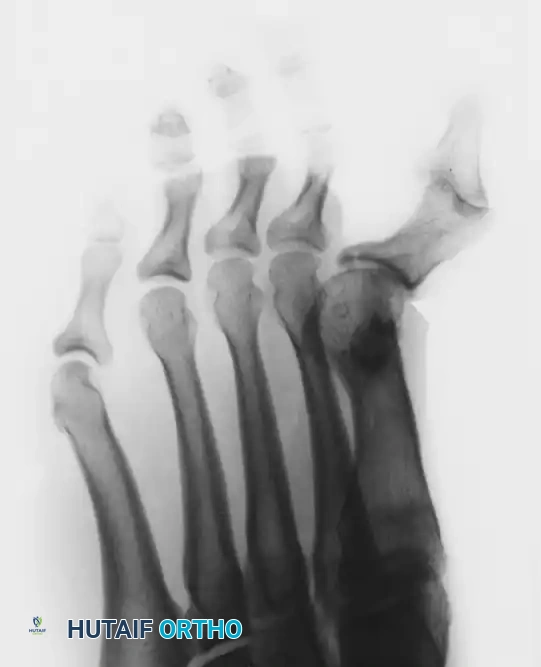

Figure 81-80: (A and B) Severe hyperextension of the metatarsophalangeal joint and hyperflexion of the interphalangeal joint, accompanied by varus and axial rotation of the hallux (the classic intrinsic minus claw toe). (C and D) This dynamic, supple deformity was successfully treated by arthrodesis of the first metatarsophalangeal joint combined with a plantar release of the interphalangeal joint to restore alignment.

This resulting deformity—the clawed hallux—is the hallmark of the intrinsic minus state. If left untreated, the soft tissues rapidly contract, converting a supple, dynamic deformity into a rigid, fixed multiplanar deformity that often necessitates salvage procedures such as first MTP joint arthrodesis to restore a plantigrade, braceable, and pain-free foot.